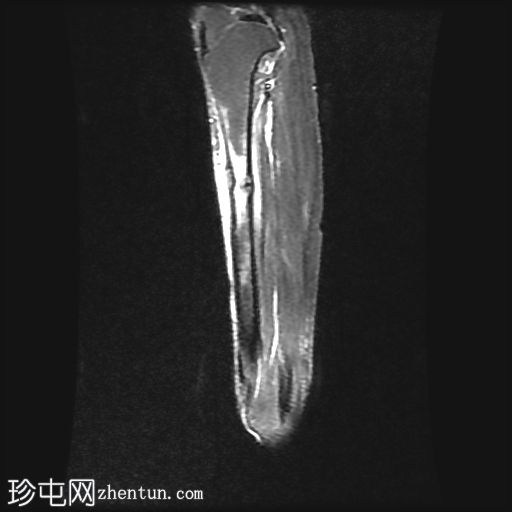

MRI

矢状位

T2加权像

内侧皮质可见一条低信号斜向皮质内线状影。

多发局灶性皮质内T2/STIR高信号病灶。皮质内可见一条线状信号异常区域。

邻近髓腔内广泛的骨髓水肿。

高等级内侧胫骨应力综合征(4b 级)表现为皮质内线性骨折线,伴有广泛的骨髓和骨膜水肿,代表皮质突破前的高级应力反应。

关键要点:4b 级骨折的定义是皮质内线性信号异常加上骨髓和骨膜水肿——MRI 对于诊断和防止发展为完全性骨折至关重要。